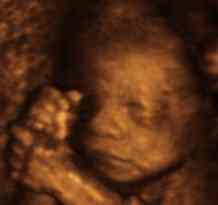

Вашето бебе сега вежба да дише во плодовата вода. Тоа ја вдишува и ја исфрла течноста од белите дробови.

Коските на внатрешното уво се стврднуваат.

Телото му изгледа попропорционално, иако главата е се уште поголема во однос на тоа кога ќе се роди.

Кожата веќе не му е толку прозирна.

Ноктите се речиси целосно развиени. Влакненцата што го покриваат неговото тело стануваат потемни.

Сега е целосно прекриено со сирестата бела материја која го обвиткува за да го заштити од плодовата вода. Оваа материја ќе се разгради пред породувањето, но ќе остане доволно за да помогне при лубрикацијата за време на породувањето.

Просечната должина на бебето е околу 29 см, а просечната тежина околу 500 грама.

Бебе во 23-та седмица на бременост